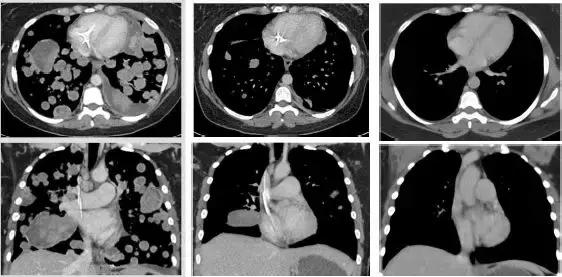

肉瘤双肺转移患者治疗前 治疗13周期肿瘤几乎完全消失!

2018年3月26号,拜耳和LOXO公司宣布已经正式完成了Larotrectinib在美国的上市申请工作,接下来,就是等待FDA的决定。预计将在2018年上半年获批上市,届时全球肿瘤医生网医学部将在第一时间报道!